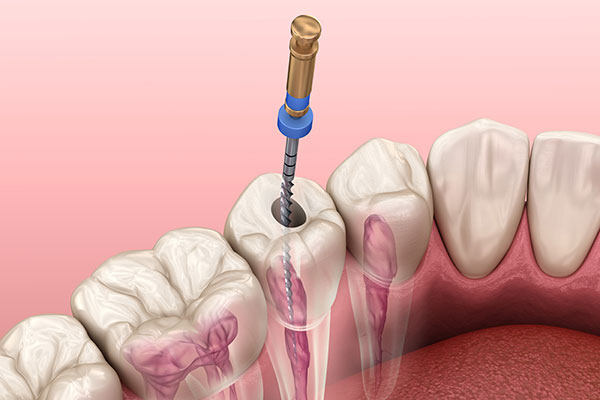

精密根管治療

当院ではマイクロスコープとラバーダム防湿を使用した精密根管治療を実施しています。虫歯菌が歯の根にある根管内の血管や神経まで感染したまま放置すると抜歯になることがあるため、感染した血管や神経を取り除く必要があります。この時に行う根管をきれいにする処置を精密根管治療といい、虫歯菌に感染した血管や神経をすべて取り除き、洗浄・殺菌した後、隙間なく薬剤を詰めて密封し、被せ物で補います。感染部を取り残してしまうと、虫歯菌の再感染や炎症の原因となるため、根管の中は徹底的に洗浄・殺菌する必要があります。マイクロスコープ用いることで、治療部を目で確認しながら治療することが可能になり、再発の少ない精密な根管治療を行うことができます。